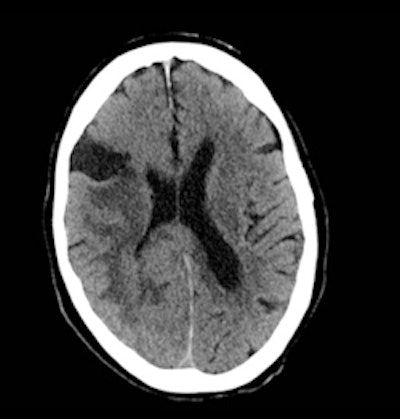

A 63-year-old person presented to the emergency department with facial asymmetry and mild left-sided weakness. After clinical assessment, the patient was referred to the stroke unit and a CT scan of the head was requested (figure 1). This was reported as showing ischemic changes within the white matter, with an area of established infarction in the region of the middle cerebral artery.

Following further clinical review, it was felt that the presentation was atypical for a cerebrovascular accident (CVA), particularly as the symptoms had been slowly progressive for two weeks. An MRI scan was requested. This demonstrated a large paracentral tumor in the right occipital lobe (figure 2). Review of the CT shows asymmetry of the gray white matter and compression of the ventricle which was not appreciated at the time of initial reporting.